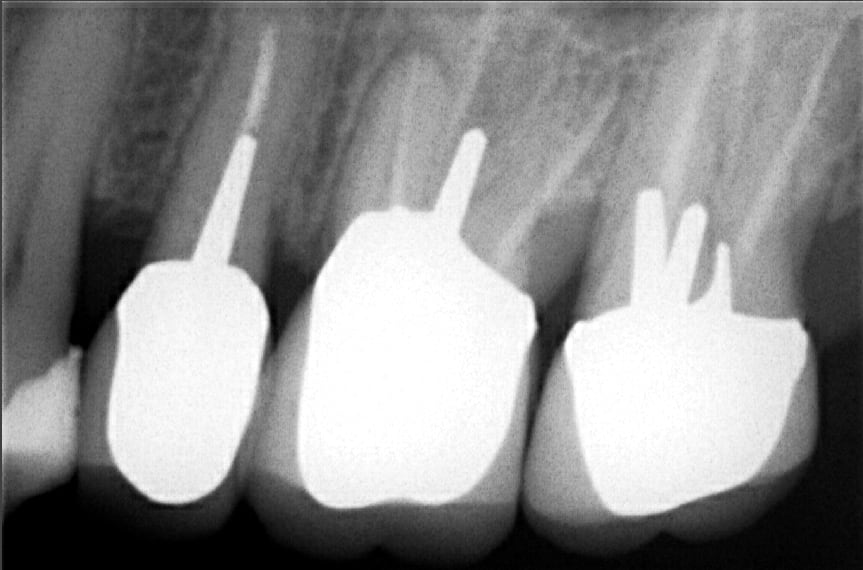

J'ai posé trois couronnes sur 25 26 27 à un patient en 2014 quand j'étais encore salariée d'une mutuelle. Le patient se plaint aujourd'hui à mon cabinet qu'il a toujours "senti" la couronne sur 26 et qu'il y a d'après un autre praticien un gros souci et tout à refaire (25 et 26) mais hors de question pour lui de repayer puisque c'est de ma faute...

J'ai proposé de déposer déjà 26 et de lui refaire, qu'en pensez vous? Que pensez vous de l'image entre 26 et 27?

Image apicale sur racine Mv de 26.

Mv2 non traité surement. Après la radio est assez floue.

d'autant plus que le tenon palatin me semble hors du canal et qu'il y a une grosse perte de substance distale et que l'image de l'apex de la racine distale n'est pas géniale

fr plus aucun des tenons de la 7 ne paraît etre dans le trajet du canal

Concernant le cas (pas sa prise en charge, évidemment direction mutuelle), la radio est floue et pas vraiment à l'apex, mais que raconte le patient exactement, parce qu'une dent que le patient "sent" sans épisode aigu en 3 ans, çà me fait surtout penser à une racine antrale (vu le sinus qu'on aperçoit entre 26 et 27 si je ne me trompe pas), pas vraiment à une lésion périapicale.

Je pense que le souci vient plutôt de l'espace inter-dentaire entre 26 et 27.

Sd du septum.

Sur la radio on voit pas les apex. Perso infoutu de dire si souci endo.

Par contre y'a une radio clarté en distal de la 6. Carie certainement.

+1 pour souci de septum.

J'aurais un avis comletement différent au vu de la radio en regardant l'axe d'insertion du tenon...

Le mv2 n'ayant pas été traité (ou n'existant pas dans ce cas), on compte 3 filets canalaires traités et un tenon hors axe...

Mais la radio est a refaire au moins dans deux incidences et complete.